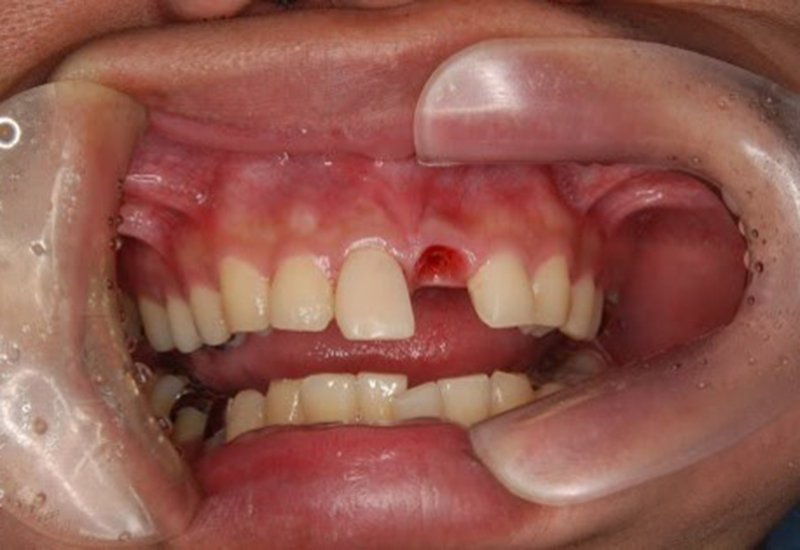

右上1 ジルコニアセット

左上1インプラント補綴セット(ジルコニア)